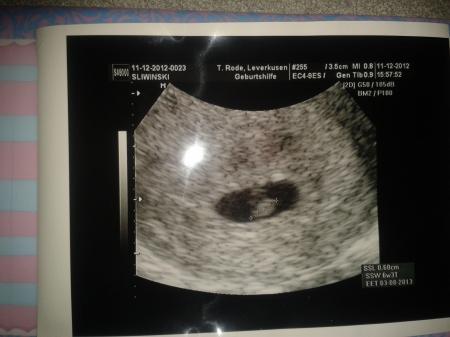

Hat schon schön gepochert. Bin ich froh und erleichtert,jetzt nur weiter positiv sein und hoffen das es Baby gut geht. Echt komisch in der zweiten ss hab ich irgend wie mehr angst das das Baby krank sein könnte als in der ersten. Liegt vielleicht dadran das beim Sohn mit Nieren u Herz was hat. So Krümel ist 6mm alles zeitgleich mit 6+3 ssw. Nächster Termin am 8 jan. am Donnerstag jetzt lässt sich mich noch krank schreiben uns dann gibt's ein BV. Ich hatte in der ersten ss Nr furchtbare Ärztin keine Aufklärung keine Untersuchung 2 US bis zu 34 ss Woche bis ich im kh gelandet bin. Dann bin ich du der Ärztin hin wo ich auch jetzt bin ,die ist echt Gold wert!! Bin heute richtig happy. Sorry langer Text:)

Krümel fast vergessen

Wahnsinn, das freut mich für dich! Das Bild sieht toll aus;) Jetzt bin ich echt bei mir gespannt, muss ja Freitag hin, mal sehen ob man bei mir auch schon was sieht, am Freitag bin ich 6+0. Lg

Wie schön Freut mich, dass alles gut ist. Richtig schönes Bildchen hast du da von deinem Krümmelchen!

Tolles Bild, schön das es euch so gut geht. LG